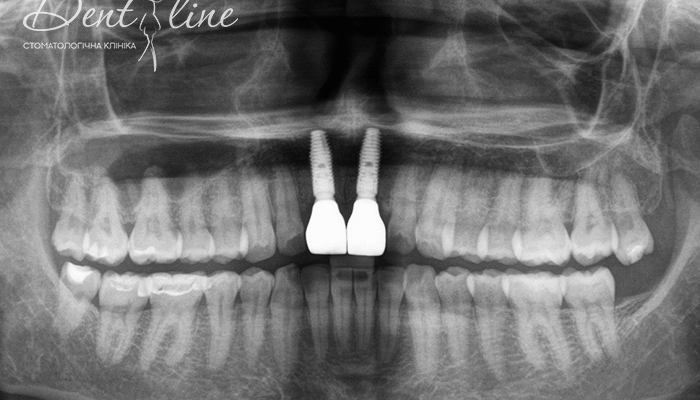

Резорбція це процес, коли тверда речовина розчиняється, переходячи в інший стан. Найчастіше цей процес застосовується у сферах медицини та біології. Наприклад, у контексті людського організму — розкладання кісткової або зубної тканини, яке відбувається під дією клітин, що руйнують мінерали.

Зветься нормальним при пересічному обміні речовин. Але коли резорбція кісткової тканини перевищує її відновлення, виникають проблеми. Остеопороз стає найгіршим сценарієм. Інші приклади включають втрату зубів через резорбцію коріння за певних умов. І таке інше…